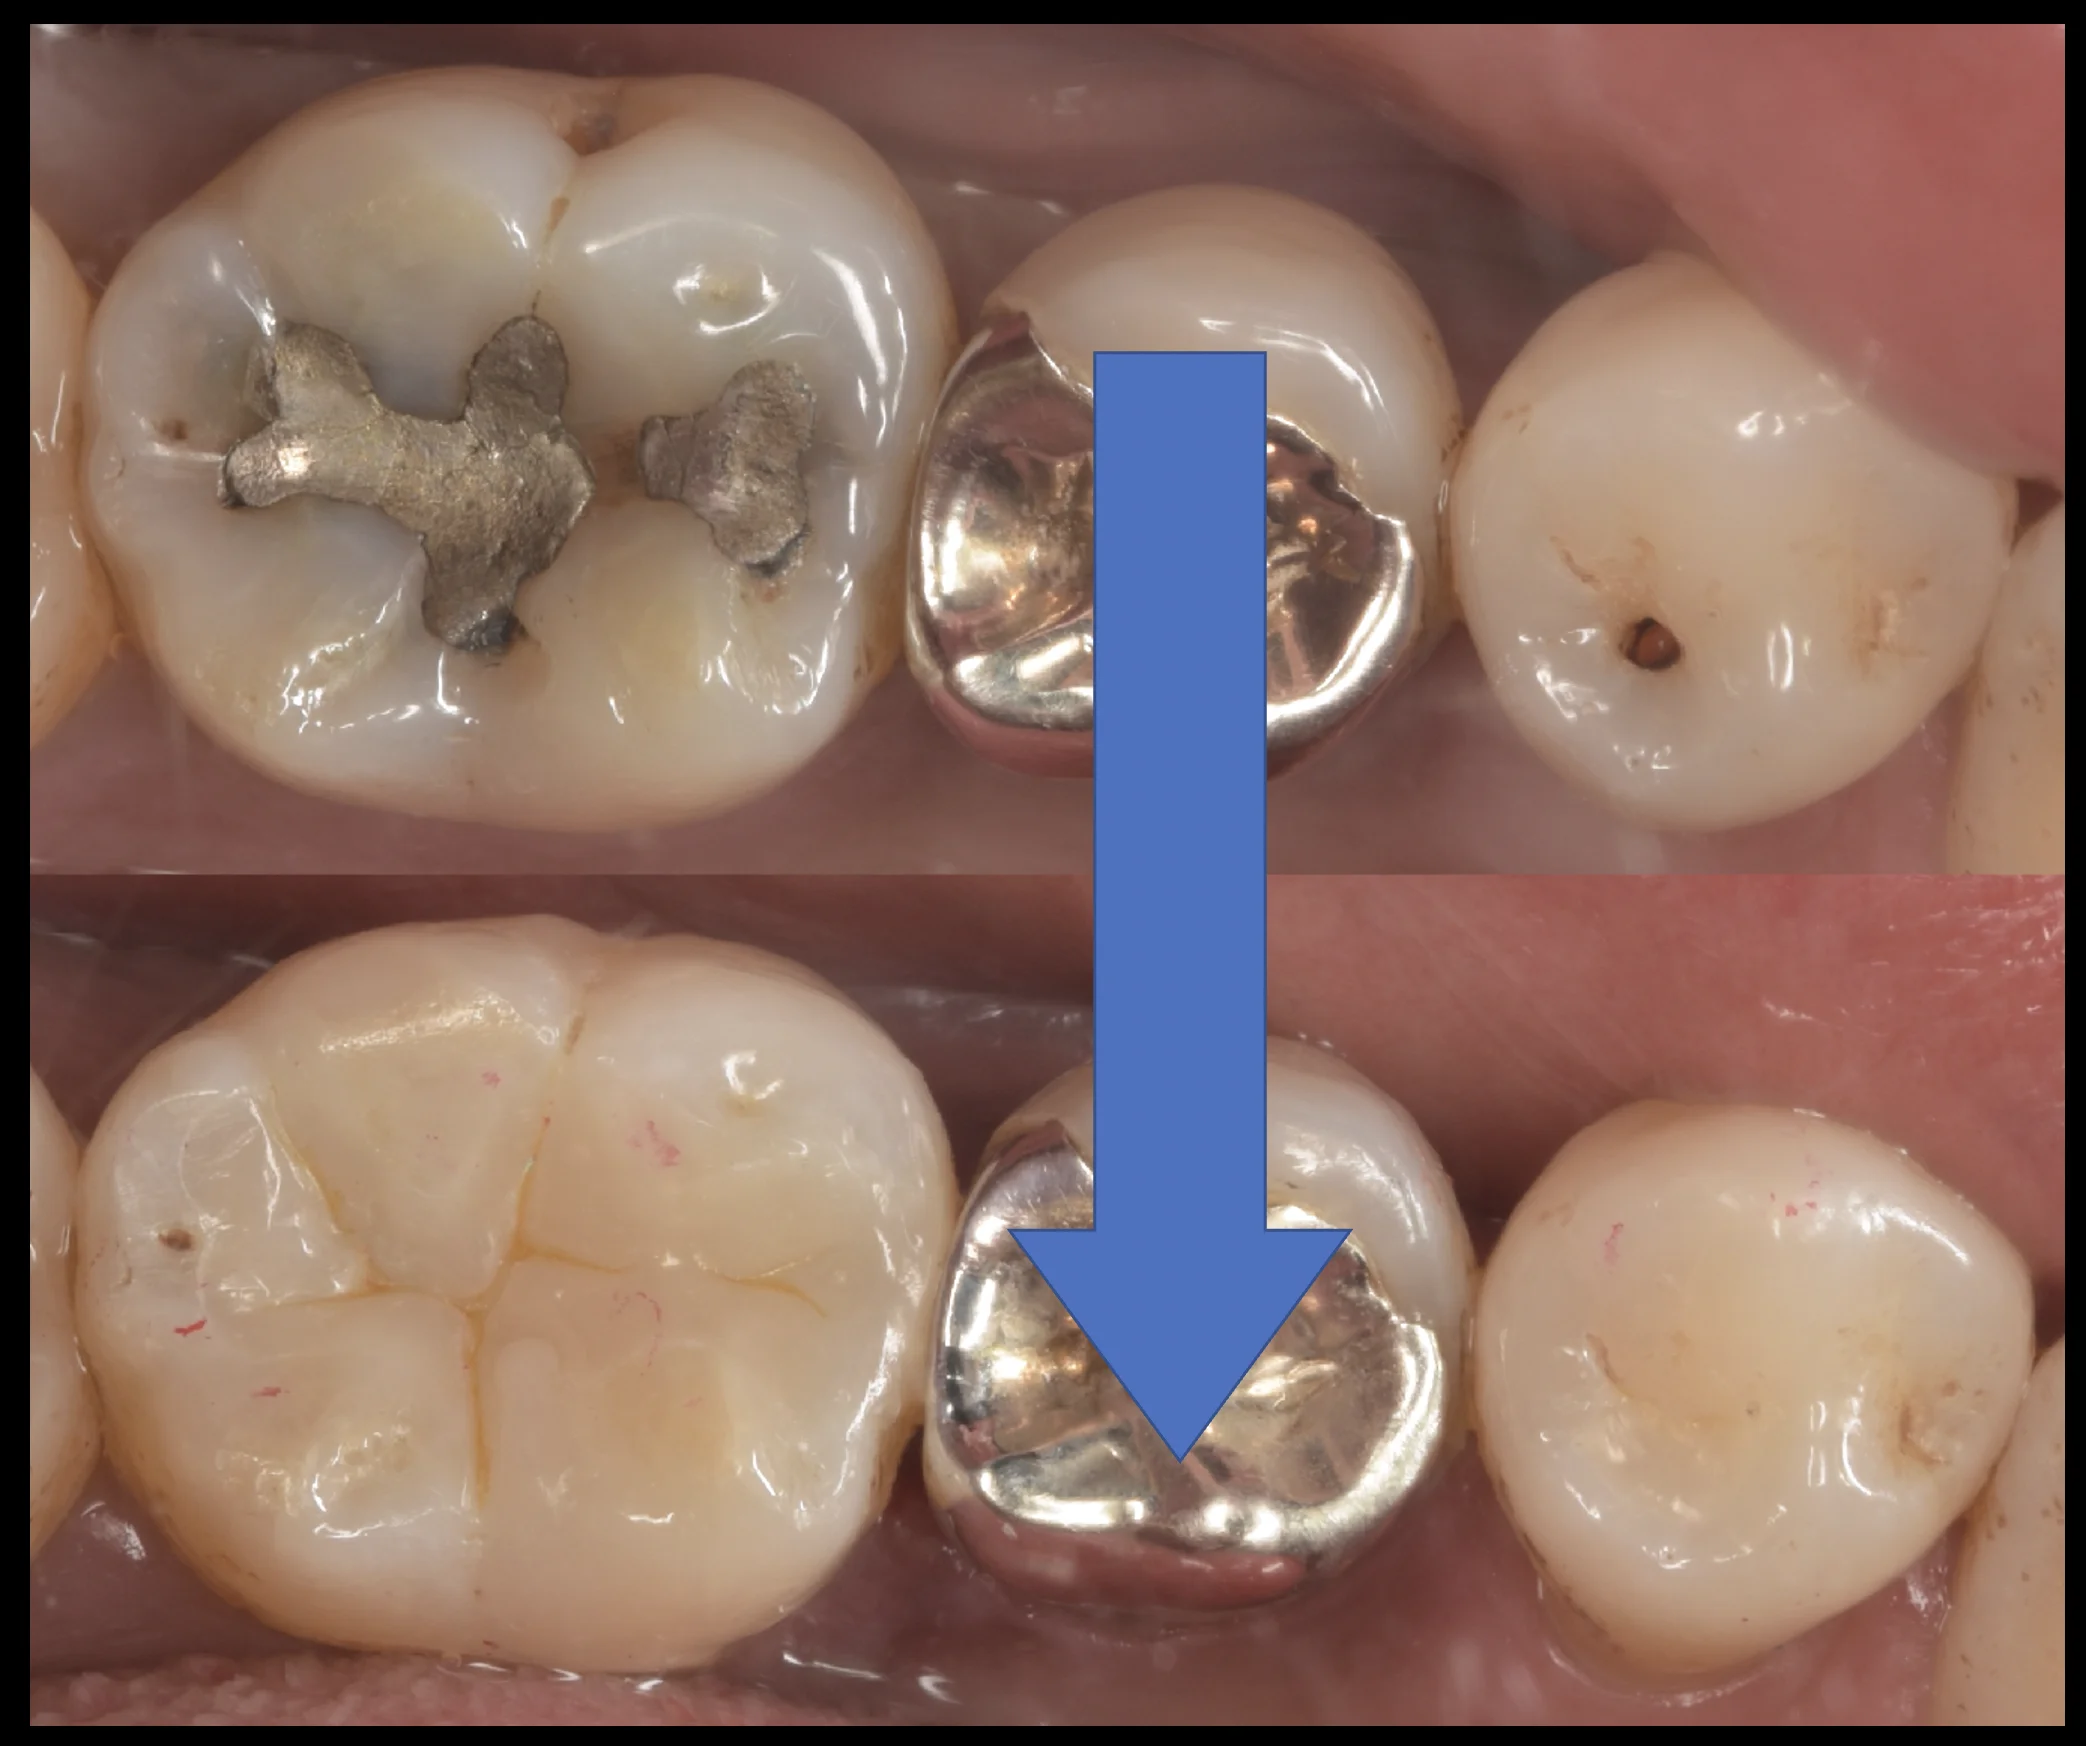

アマルガムを除去し、右の歯の虫歯を見やすくしたのがこちらになります。

左の歯の内部が真っ黒になっており、右側の歯についてもそこそこ内面が黒く広がっているのがわかるかと思います。

そして虫歯を取り切ったのがこちらになります。

ところどころ黒い部分が残っていますが、この場所自体は虫歯ではありません。

ただ着色がついている部分についてはダイレクトボンディングの接着強さを優位に低下させるためなるべくなら取り切った方が持ちはよくなるため、私はできれば取り切るようにしています。

ただし、今回はこれ以上除去した場合、神経にダメージが入りそうだと判断し、一部着色している部分を温存しています。

虫歯自体は完全に取り切れているのでその点は問題はありません。

そして詰め終わったのがこちらになります。

いかがでしょうか?

違和感なく仕上げられたかと思います。

左側については詰めた部分がまだわかりやすくなっていますが、これは歯の乾燥が原因のため、1週間くらいして歯に水分が戻ると色としては違和感がなく合ってきます。

左はやや大きいですが、右の歯の虫歯は非常に小さいため、予後としては右の歯の方が相当に長期的に使えると予想できます。

実際歯の間に入っていない、右の歯のような虫歯は当院でも先代から20年以上持っているケースも珍しくないため個人的にはやはり小さければ小さいだけダイレクトボンディングで治療するメリットは大きいなと感じています。

治療の術前術後がこちらになります。

長時間の治療お疲れ様でしたヽ(゚∀゚)ノ パッ☆